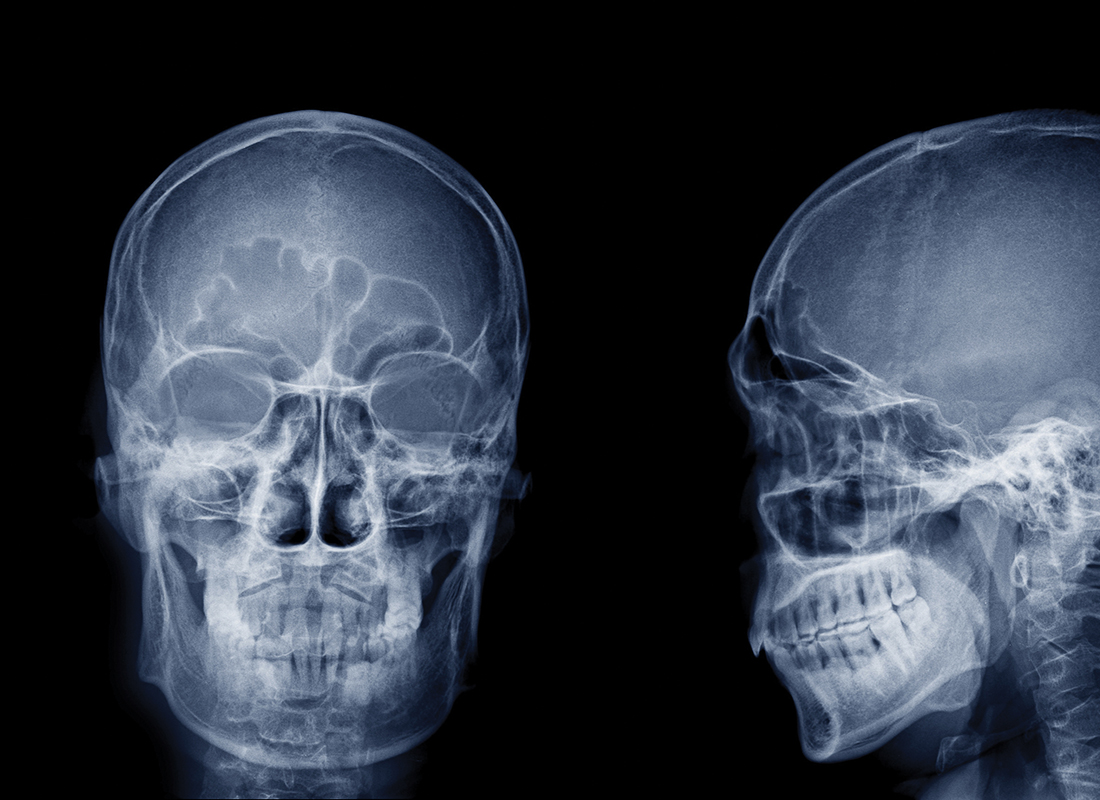

History shows how medicine is in constant flux. Many great minds have focused on staving off death’s inevitable call and improving the lot of the sick. For example, Wilhelm Roentgen’s work with X-rays in late 1895 triggered one of medicine’s most dramatic journeys: the birth of what we now call ‘clinical radiology’.

Since then, we have refined diagnostic imaging so that it is at the heart of many clinical pathways. New ways to probe the body and see inside are emerging all the time.

The seminal change was driven by the increasing digitisation of images, first at machine level, until those datasets drove powerful diagnostic tools in ways Roentgen could not possibly have imagined.